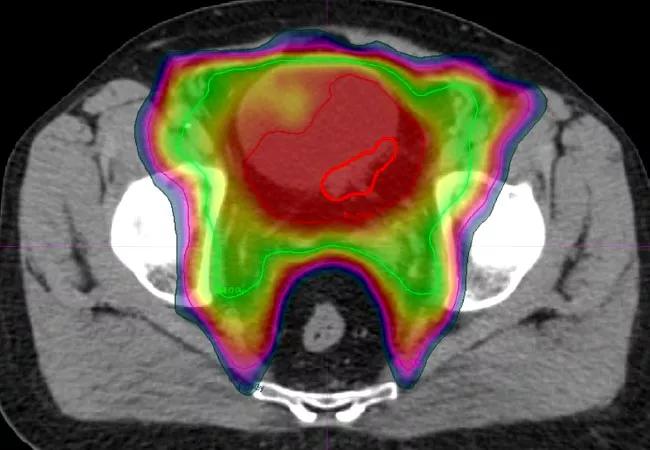

In the TMT approach, radiation oncologists typically deliver 40-45 Gy to the entire bladder, prostatic or proximal urethra and the adjacent lymph node basin in the pelvis, followed by a restaging cystoscopy with repeat TURBT and biopsies.

Planning CT scan for concurrent chemoradiation therapy following maximal TURBT in a bladder cancer patient; radiation dose graded by color. The red outline encircles tumor location.

If a patient demonstrates complete response, concurrent chemoradiation continues to a total dose of 64-65 Gy. A minority of patients either fail to respond or progress during chemoradiation. In such patients who display aggressive resistant histology, immediate salvage radical cystectomy is recommended.